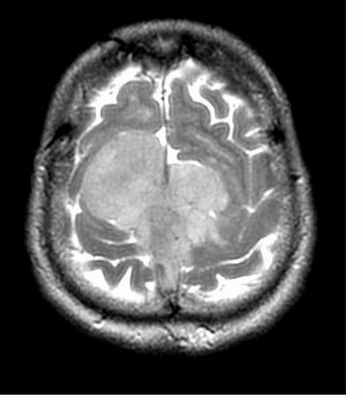

МРТ головного мозга. Менингиома серпа. Аксиальная и корональная Т1-взвешенные МРТ с контрастированием.

МРТ головного мозга. Менингиома верхнего сагиттального синуса. Аксиальная Т2-взвешенная МРТ и сагиттальная Т1-взвешенная МРТ и сагиттальная МР-венограмма.